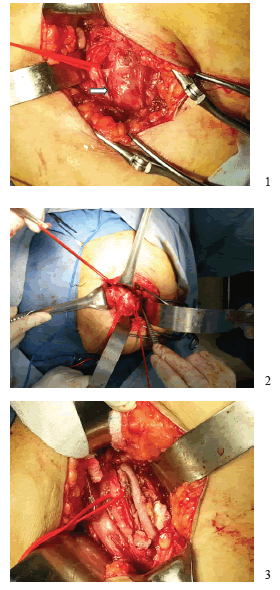

Fue sometida a cirugía: por la vía A (en decúbito supino), se extrajo el injerto de la safena mayor en el muslo derecho; por la vía B (en prono), se hizo una incisión oblicua en el glúteo derecho, se hizo la disección por planos y de las fibras del músculo glúteo mayor, exponiendo las venas glúteas y el nervio ciático superpuestos y adheridos al aneurisma de la arteria ciática persistente. Se liberó el nervio y se ligó la vena. La arteria se disecó y reparó en sus porciones, proximal y distal al aneurisma.

Se administró una dosis intravenosa de 6.000 UI de heparina no fraccionada, y se procedió al pinzamiento y la apertura longitudinal del aneurisma, la extracción de los trombos y la reconstrucción con el injerto de safena invertida (figura 3). Al final de la cirugía, se confirmó la presencia del pulso poplíteo derecho, con buena intensidad.

adherido (flecha). 2. Control proximal y distal del Aneurisma de

arteria ciática persistente 3. Reconstrucción con injerto de vena

safena invertida.